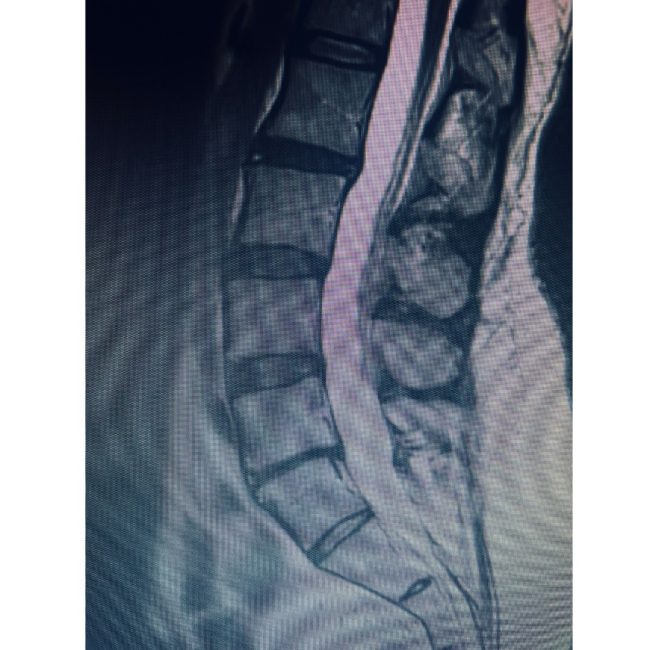

Comprehensive Anterior–Posterior Fusion Restores Alignment and Function for L4–5 Deformity

👉 Spinal deformities / Anterior-posterior (front-back) Spinal Fusion — At Texas NeuroSpine Surgery, our goal is to always find the least invasive approaches for the best surgical outcome. However, some cases require more extensive approaches, as in this case of an L4-5 deformity in a patient with rheumatoid arthritis and years of debilitating low back…